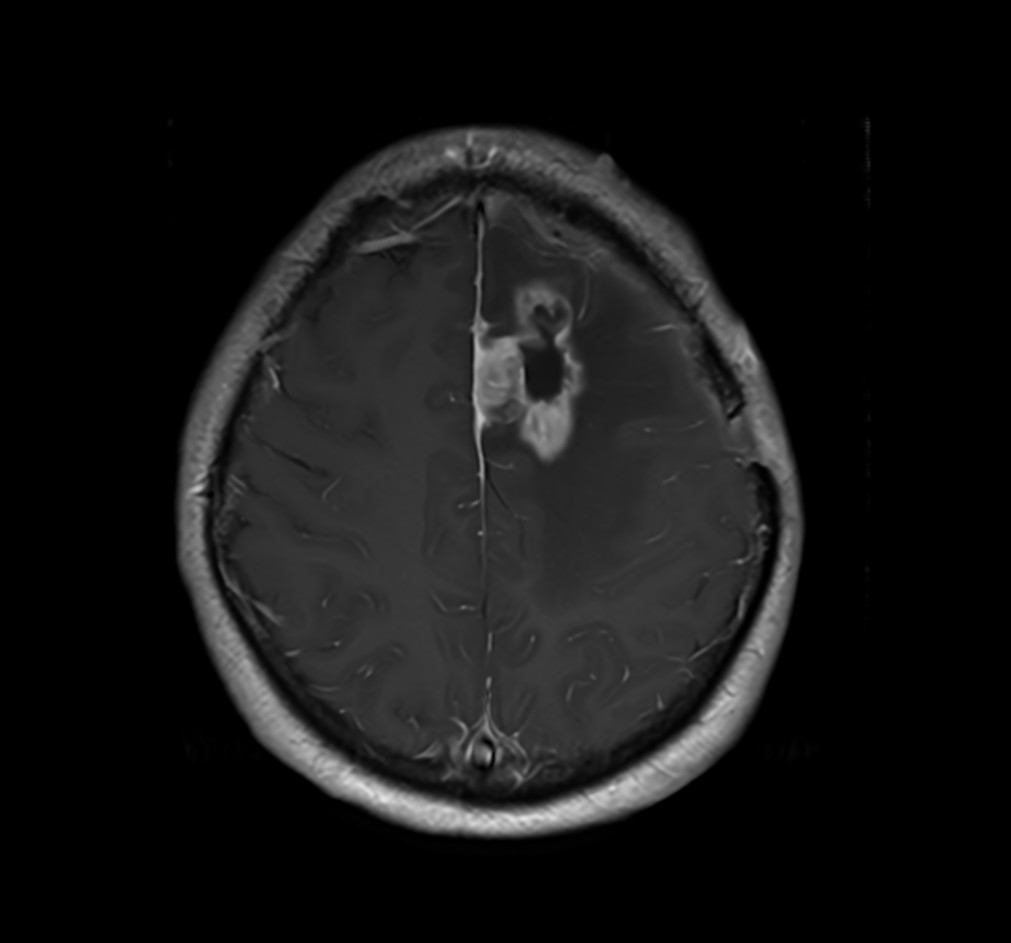

SmartSpeed Precise imaging for brain with glioblastoma

Kyushu University Hospital Japan